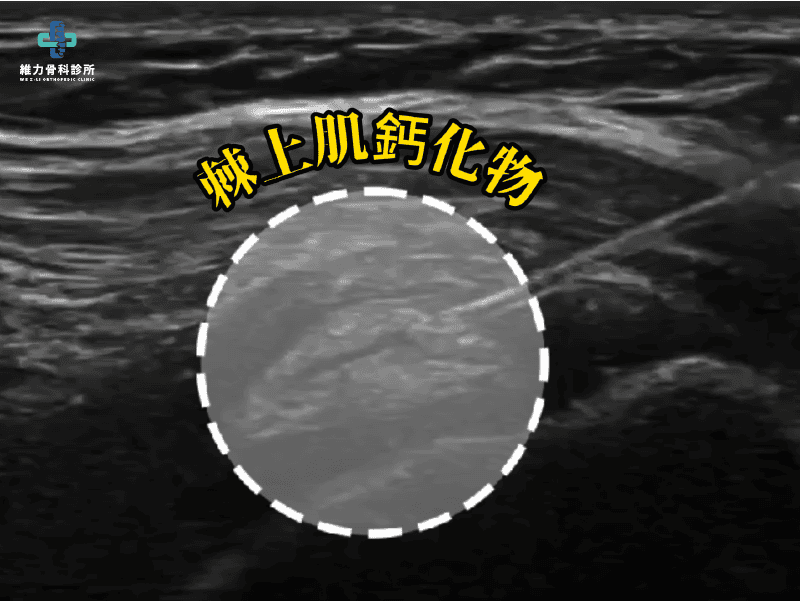

左肩疼痛與活動不順就診,影像與臨床評估顯示為左側上臂鈣化性肌腱炎,主要影響棘上肌(SSP),疼痛已影響日常動作與肩部活動度。

陳小姐因左肩疼痛與活動不順就診。影像與臨床評估顯示為左側上臂鈣化性肌腱炎,主要影響棘上肌(SSP),疼痛已影響日常動作與肩部活動度。

- 主要疼痛來源以肌腱鈣化為主

- 治療方式:超音波導引下鈣化沖洗(Calcification Lavage)